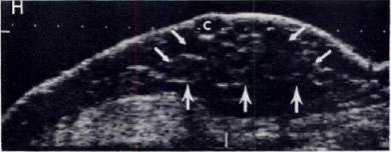

| Above, 32-year-old man undergoing treatment for brain tumor complained of soreness in the left breast. A sagittal sonogram through left areolar region. Expanding focal hypoechoic area (arrows) in subareolar area secondary to focal gynecomastia. Below, 59-year-old man who underwent modified left radical mastectomy for adenocarcinoma of the breast. A sagittal sonogram of right breast shows sebacious cyst and early changes of diffuse gynecomastia. Wigley KD, Thomas JL, Bernardino ME, Rosenbaum JL, "Sonography of gynecomastia" (AJR 1981; 136:927-930). |